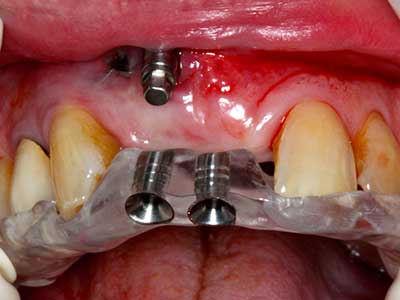

Piezo surgery has additional advantages when harvesting bone blocks. In addition to the high precision with osteotomy described above, the use of the thin saw tips specifically minimizes loss of material. Greater loss of material during harvesting can be expected with the thicker instrument tips, particularly when using Lindemann drills (Lakshmiganthan, Gokulanathan et al. 2012). The basal separation, which is necessary particularly for retromolar block transplants, is simplified by specially designed rectangular saws, with the result that piezo surgery is viewed as a precise, simple and safe procedure for harvesting retromolar bone blocks (Happe 2007) (Fig. 1-12).

Indication: Bone splitting

Bone tissue is not simply a mineral structure but also contains a substantial proportion of collagen fibres. This means it not only has good compressive strength but also a degree of flexibility, which can be taken advantage of when performing bone augmentations. In the classical expansion procedure using bone splitting, the atrophied alveolar ridge is split longitudinally and carefully expanded after reaching an adequate osteotomy depth (Fig. 13-16), ideally without substantial removal of the periosteum (Brugnami, Caiazzo et al. 2014, Stricker, Fleiner et al. 2014). Screw and plate systems with increasing expansion distance have proven effective in separating the two bone lamellae while remaining below the fracture threshold. In general, residual bone widths of at least 3–4 mm are required (Chiapasco, Zaniboni et al. 2006) to guarantee adequate flexibility and sufficient bone coverage of the future implants. If necessary, a vertical relief osteotomy on one or both sides can improve flexibility. A combination with additional augmentation techniques, particularly on the buccal side, has been described as an alternative to the classical technique.

The splitting procedure is particularly atraumatic and there is no significant loss of dimension when using piezosaws, and there are no significant differences between implants in split jaws and implants in an alveolar ridge without a bone deficit (Chiapasco, Zaniboni et al. 2006, Danza, Guidi et al. 2009). However, sufficient continuous irrigation is essential, particularly with locally restricted and deep splitting to prevent thermal stress in the apical osteotomy regions.